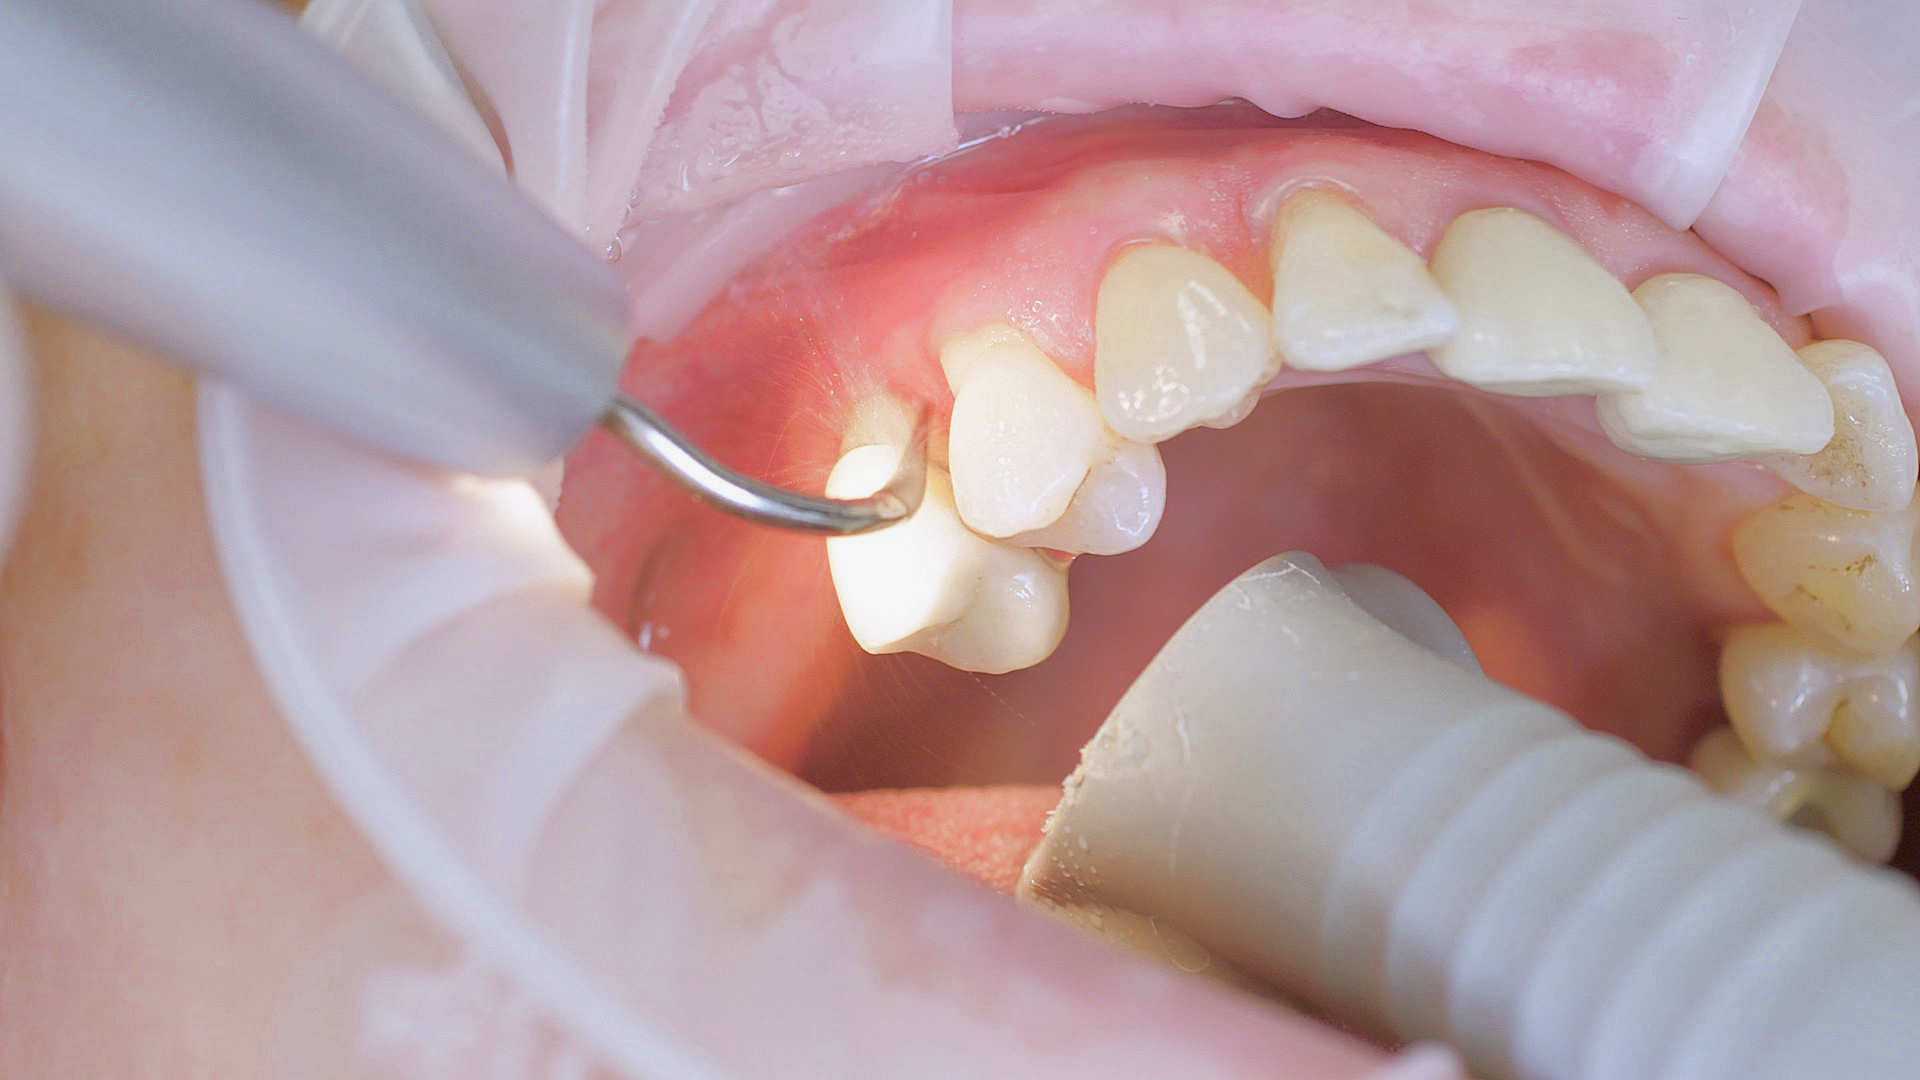

Every dental examination is based on a detailed medical history combined with targeted diagnostics con- taining as much detail as possible: The dentist records systemic risk factors such as diabetes or smoking and identifies any potential increased tendency to inflammation.[3] Hard and soft tissues are examined and periodontal pockets are probed in a screening test according to PSR (Periodontal Screening and Recording). In case of abnormal findings, the periodontal status is then re- corded and therapy is initiated where necessary. This treatment begins with professional biofilm management, by using, for example, rotary cups and polishing com pounds (Fig. 1), and comprehensive instructions in oral hygiene. Sonic or ultrasonic systems remain an effective alternative or supplement to manual instruments for sub- gingival debridement and biofilm management (presentation by Prof. Dr Ulrich Schlagenhauf;

Fig. 1: Good individual oral hygiene and professional biofilm management, e.g. with cups and brushes, helps support periodontal and peri-implant health.